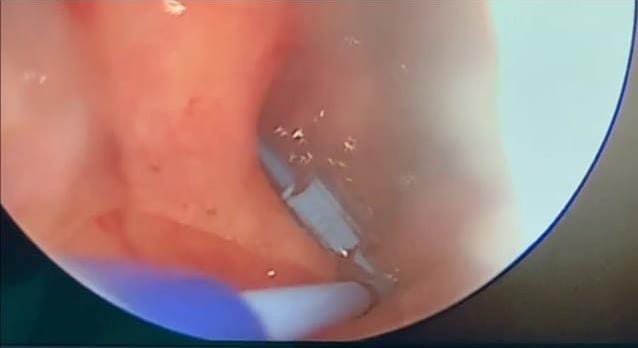

“என்டொஸ்கொபி

யுஸ்ட்ச்ஷியன் டியுப் சேஜரி”

(Endoscopic eustachian tube surgery) எனும் சத்திர சிகிச்சை இலங்கையில் முதன் முதலாக நீர்கொழும்பு மாவட்ட பொது வைத்தியசாலையில் செவ்வாய்க்கிழமை (21) இடம்பெற்றது.

இந்த புதிய முறையின் மூலம் மூக்குத் துவாரத்தின் ஊடாக கமராவை அனுப்பி காதுக்குழி குழாய் மூலம் சலி, சீல் என்பன அகற்றப்படுகின்றன. இச் சத்திர சிகிச்சைக்கு சுமார் 30 நிமிடங்கள் எடுக்கும் என்றார்.